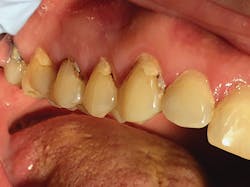

We use SDF in our office as an alternate treatment option for medically challenged patients and older adults. As our heavily restored older patients become more restricted in their ability to perform daily hygiene routines, such as brushing teeth and flossing, we start to see more marginal and root surface caries. The cause of this can be twofold: lack of proper plaque removal and poor diet. When interviewing patients in this age group or their caregivers, we find patients tend to experience dry mouth and often find relief from sipping on sugary beverages or sucking on hard, sugary candies. In a dry mouth, these habits accelerate tooth decay. Compromised medical situations often prevent patients from undergoing dental treatment.

As dental providers, it is our responsibility to educate patients and their caregivers and provide treatment options. For a patient who is in the last stages of dementia, it is neither ethically nor morally appropriate to put them through extensive restorative procedures or extractions. In our office, we place SDF at the initial diagnosis of decay after removing food debris and plaque, and then we reapply it at subsequent appointments. If the caregiver requests, we can follow up with treatment at the assisted living facility. SDF shows success with annual applications, but in our practice, we have seen greater benefits if SDF is reapplied at six-month intervals during the first two years. We attribute this to the difference in home-care plaque removal, habits, and diet, which are often uncontrolled in real-life situations, as compared to clinical trials.